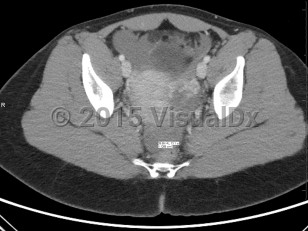

Ectopic pregnancies are found in reproductive-age patients. Risk factors include prior ectopic pregnancy, history of endometriosis or tubal infection (pelvic inflammatory disease), pregnancy occurring in the setting of current use of a progesterone intrauterine device (IUD), history of tubal surgery, advanced maternal age (aged 35 years or older at time of due date), and tobacco use. It is also important to note that over 50% of all patients diagnosed with an ectopic pregnancy have no known risk factors.